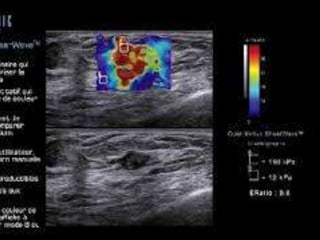

 Elastography has the potential to

differentiate complicated cysts form

solid masses.

 Shear-wave propagation does not occur

in cysts and therefore cysts should have

elastography values of zero and will

appear mostly black or homogeneously

blue on the color overlay elastogram

Large simple cyst which shows no elasticity within the lesion and

hence black